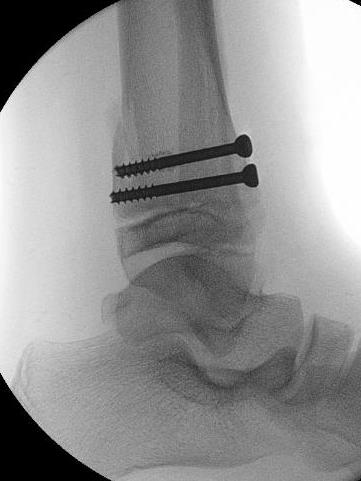

Technique

Anterolateral incision

- reduce fracture / articular surface

- epiphyseal screw lateral to medial / medial to lateral

- preserve physis